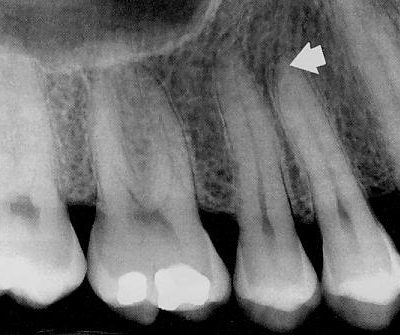

Radiogramos atliekamos mažo radioaktyvumo rentgeno aparatu. Radiogramos reikalingos įvertinti aplink dantis esančius audinius, nustatyti šaknų kanalų buklę prieš protezavimą, taip pat endodontinio gydymui ir jo kokybei įvertinti. Radiologinio tyrimo metu pacientas maksimaliai apsaugomas nuo tiesioginių ir išsisklaidžiusių rentgeno spindulių – naudojamas mažiausias spinduliuotės kiekis pakankamai diagnostikai.